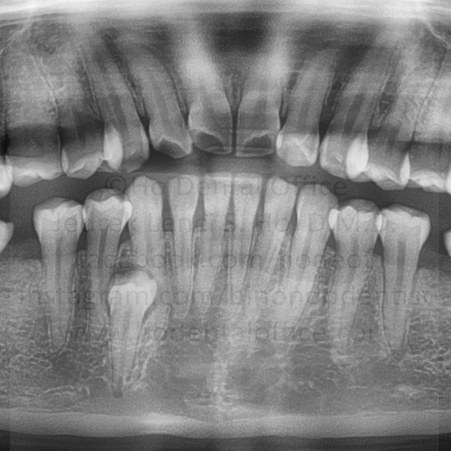

Impacted tooth are tooth that have not erupted normally in the mouth. The most common reason for it is because of a lack of space in the mouth. In most cases, they have no function in the mouth since they are out of occlusion. Therefore, it is advisable to remove them, the earlier the better, in order to avoid complications in the future.

Odontectomy is the dental procedure entailing the removal, usually with surgical intervention, of impacted tooth, usually the third molars. It is one of the most common minor oral surgical procedures in dentistry.

The most common teeth to be impacted are:

third molars (or wisdom tooth) - lowerupper

premolars - lowerupper

second molars - lowerupper